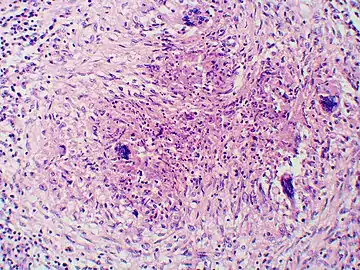

Granuloma with early suppuration. Fungal organisms difficult to recognize at this low magnification.